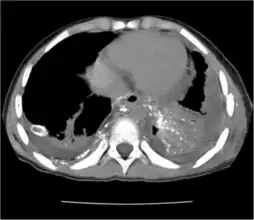

Left chylothorax with chest tube drainage -

CT scan showing extensive chylothorax caused by leakage from the thoracic duct -